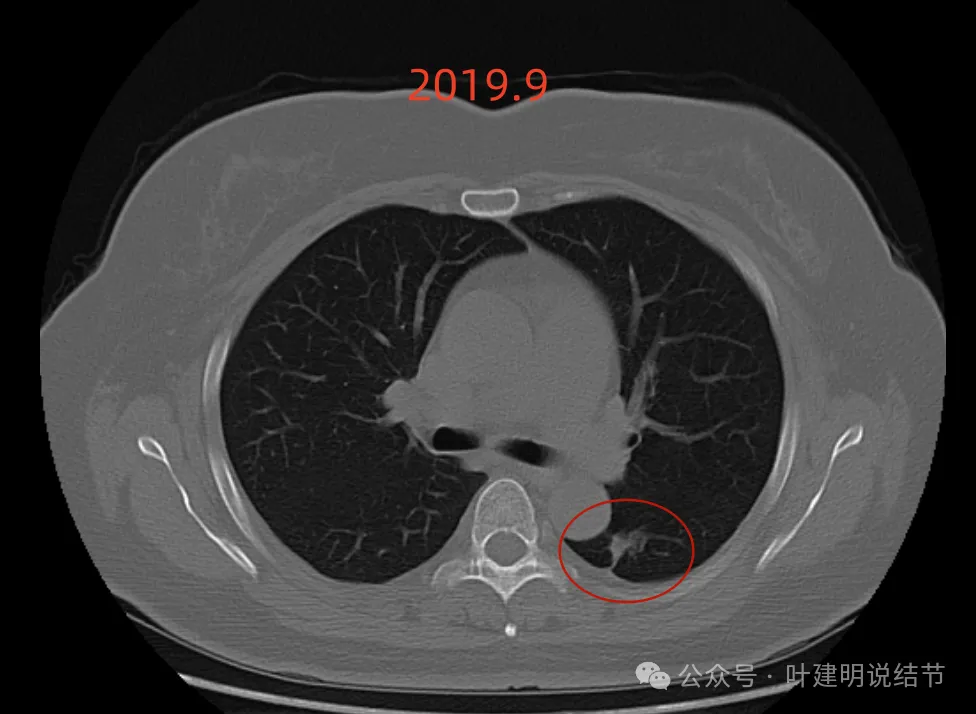

先看2019年时的影像:

病灶出现,密度不纯,有点状高密度成分,表面不光滑不平整。

实性成分为主,但边缘缺乏膨胀性,长刺较细长,感觉更像慢性炎。

此层不是很像炎症,有一定膨胀性。黄色箭头处示有细支气管被病灶截断似的;紫色箭头示略有小的毛刺征;但绿色箭头所指的胸膜有增厚的表现,而且蓝色箭头指的条状不锐利,这又与炎性病变并影响邻近胸膜是符合的。

上图密度较高,大部分实性,灶内略杂乱,与主动脉壁之间稍有缝隙,对应胸膜略有增厚,整体轮廓较清。

这样的病灶首次发现,虽不能完全除外恶性,但慢性炎的解释相对更符合些,肯定是要先随访观察或消炎后复查再对比。